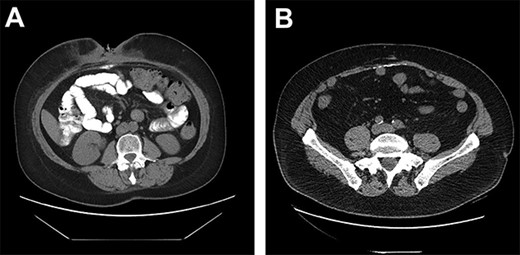

(A) DC misinterpreted as extra luminal contrast consistent with a fistula. (B) DC distributed horizontally along the hernia graft in a patient where CSAB were used.

A 59-year-old female developed an incisional hernia following an open hiatal hernia repair. She underwent a repair with polypropylene mesh that was complicated by a mesh infection that required partial mesh explantation. Two years later, she re-presented with a recurrent midline incisional hernia. Her risk factors for infection included prior mesh infection, smoking and a body mass index (BMI) of 35. The hernia fascial defect measured by CT was 15 cm wide with a length of 10 cm. Pre-operatively, the patient quit smoking. One month prior to surgery, she underwent Botox injection of the abdominal muscles to facilitate fascial reapproximation. At surgery, bilateral anterior component separation with release of the external oblique muscles was performed, the fascia was closed primarily and the repair was reinforced with a 20 cm×30 cm porcine submucosa hernia graft (Biodesign® Cook Medical Ltd, Indiana, Unites States), placed intraperitoneally and anchored circumferentially with interrupted full thickness absorbable, monofilament sutures (#1 PDS® Medtronic Ltd., Dublin, Ireland). Stimulan 20 cc CSAB infused with vancomycin 4 gm and gentamicin 240 mg were utilized, with half of the beads placed on top of the mesh, below the fascia and the other half on top of the fascia in the subcutaneous space. We left a drain below the fascia on the mesh and one on each side deep to the subcutaneous flaps. We approximated the skin with a running 4–0 absorbable monofilament suture (Monocryl® Ethicon, Georgia, USA) and applied a Prevena™(KCI Technologies Ltd, San Antonio, Texas) negative pressure dressing over the incision. Operative time was 3 h 11 min. The patient had an uncomplicated early recovery and was discharged home on postoperative day 5. The patient returned 2 weeks later with a superficial wound dehiscence that was managed with negative pressure wound dressing. Five months later, the wound had still not completely granulated in and a CT scan demonstrated a (6×8 cm) abscess between the fascia and the mesh. The fascial closure remained intact and the abscess was managed by percutaneous drainage. Cultures demonstrated Candida albicans and the patient was treated with an 8-week course of fluconazole. During this time the percutaneous drainage ceased and the drain was removed. The patient presented to the emergency department 7 months later with worsening abdominal pain and a CT scan was performed (Fig. 1A). The report noted ‘an abnormal collection of oral contrast lying within the base of the anterior midline indicating there is a fistulous track communicating with an adjacent small bowel segment’. On the basis of the CT findings, she was advised by the on-call surgeon that she needed emergency surgery, mesh explantation and segmental small bowel resection. However, there was no clinical evidence of enteric discharge through the wound and the patient remained well with no fever and no elevation in white blood cell count. In consultation with the original surgeon, it was decided to forego emergency operative exploration and continue conservative management. Two months later, the subcutaneous wound had still not completely granulated and an exploration and debridement under general anesthesia was performed that failed to demonstrate an enteric fistula. The wound was eventually managed by local skin flap advancement.

Only two cases of DC in incisional hernia repair have been previously described, both involving polypropylene mesh [6–8]. Both these cases described the calcium deposited in a vertical manner along the linea alba. Although it is rare for DC to be clinically relevant, it has been estimated that some degree of calcinosis occurs in up to 25% of laparotomies, usually as a punctate deposit in the midline, or along suture points of the anterior or posterior rectus sheath [9]. In our series of 23 patients undergoing incisional hernia repair with porcine submucosa hernia graft and CSAB, 6 of the 11 patients (55%) who had a post-operative CT had evidence of DC occurring horizontally along the hernia graft insertion plane (Fig. 1B).